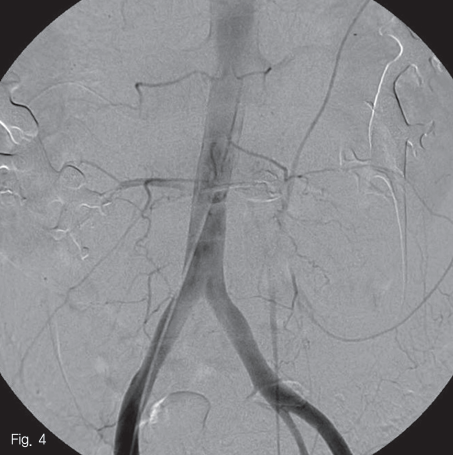

Microcatheter(Progreat; Terumo, Tokyo, Japan)를 사용하여 이 동맥을 초선택(superselection)한 뒤 N-butyl-2-cyanoacrylate(Histocryl; TissueSeal, Ann Arbor, Michigan, US)과 Liopiodol을 1:2 비율로 섞은 용액(33% glue)으로 색전술을 시행하였고, 거짓동맥류가 소실됨을 확인하였다(Fig.4).

Fig 4

Postprocedural angiogram demonstrated no further contrast extravasation from the bleeding artery after embolization using 33% glue.